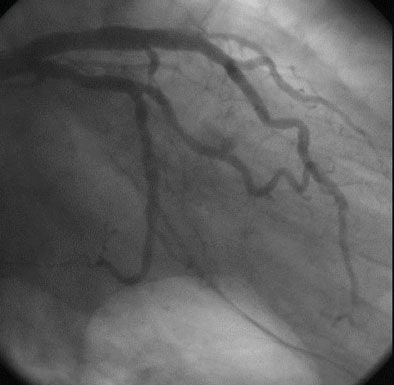

In images of a 62-year-old patient who underwent a heart transplant in 1999 due to cardiomyopathy, a heart rate of 115 bpm did not render the CT data nondiagnostic.

On CT "we observed on the axial images mixed plaque in the distal portion of the main LAD (left anterior descending), calcified soft plaque … at the LAD, and correlation between (CT and) IVUS where we observed the soft portion of the plaque," Carrascosa said. "On digital angiography we cannot determine any stenosis on distal portion of main LAD so this is a negative finding for conventional angiography in correlation with (MDCT)."

| Top to bottom: Endothelial proliferation in a transplant patient. Above, normal digital angiography . Below, MDCT multiplanar curved reformation of left main artery and left anterior descending artery; arrow points to area of endothelial proliferation. Next, IVUS followed by (bottom) axial CT image at the same level demonstrating endothelial proliferation. All images courtesy of Dr. Patricia Carrascosa. |

In a second example, a 60-year-old patient who underwent a heart transplant in 2000 due to systemic cardiomyopathy had subtle endothelial proliferation in the artery that could be seen in the multiplanar reformatted image of the right cerebral artery, which was correlated to the IVUS images. The intimal proliferation "does not produce stenosis, but it's diffuse and we see the vessel with (a smaller) diameter," Carrascosa said.